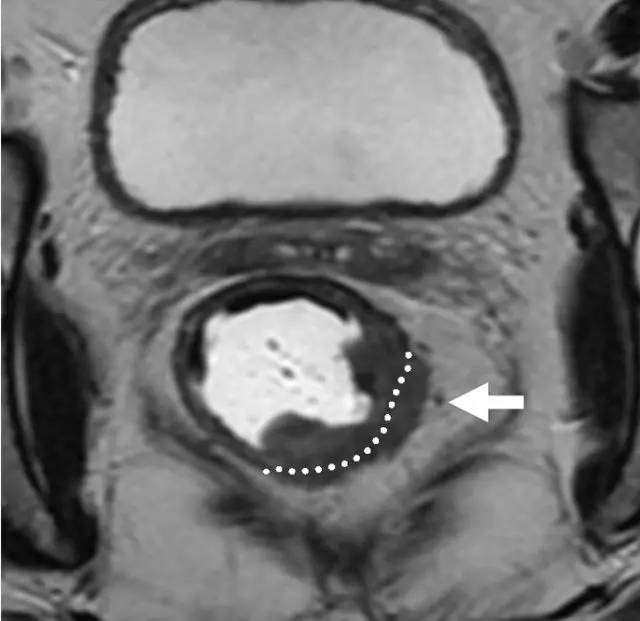

图 29 轴向 T2 加权图像报告 CRM 的距离。虚线描绘了直肠系膜筋膜,这是 T3a 肿瘤的 CRM,预测 CRM 阴性